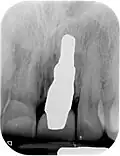

Область с единственным отсутствующим зубом

Через десну делается разрез, и лоскут ткани откидывается, чтобы показать кость челюсти.

Как только кость обнажена, серия упражнений создаёт и постепенно увеличивает участок (называемый остеотомией) для установки имплантата.

Крепление имплантата превращается в остеотомию. В идеале он полностью покрыт костью и не имеет движения внутри кости.

Формирователь десны (опора для заживления) прикрепляется к креплению имплантата, а лоскут десны накладывается на заживляющий абатмент.